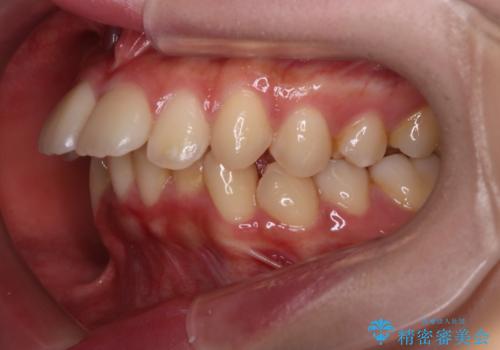

【インビザライン】アンカースクリューを用いた遠心移動

- 前歯の突出を主訴に来院されました。

アンカースクリューとインビザラインを用いて遠心移動を行うことでできる限り前歯を下げて叢生の改善を行いました。